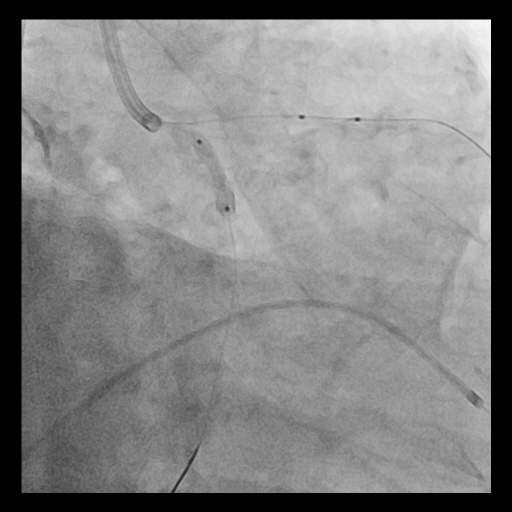

Procedural Step

Given the extensive and concentric calcium across the LM bifurcation, an upfront ¡°Rotatripsy¡± strategy (rotational atherectomy followed by intravascular lithotripsy) was selected. A 1.25 mm burr was used for initial channel creation in the LCx and LM-LAD, with transient bradycardia requiring temporary pacing. Post-rotablation IVUS revealed residual deep calcium. Subsequently, intravascular lithotripsy (IVL) using a 3.5–4.0 mm balloon (1:1 sizing to proximal LCx and LM) was applied with 8 cycles, achieving clear calcium fracture on IVUS. Two DES were implanted sequentially (LCx: 3.5¡¿28 mm; LM–LAD: 4.0¡¿38 mm), followed by high-pressure post-dilation and final kissing balloon inflation. Final IVUS confirmed optimal stent expansion (MSA: LCx 7.7 mm©÷, LAD 12.1 mm©÷, LM 13.2 mm©÷) and well-apposed stents throughout the bifurcation.